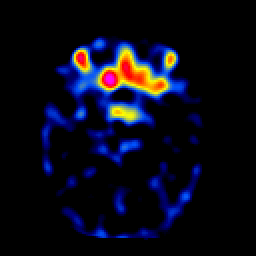

SPECT TL Study #2 -- Slice #19

[Home][Help][Clinical][Tour 1][Tour 2][Tour 3] Slice 19